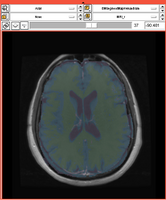

Existing Tasks in Slicer 3.6.3

Task 01: MRI Human Brain for non-skull stripped T1 scans

Task 02: MRI Human Brain Parcellation for skull stripped T1 scans

Task 03: Non-Human Primate for skull stripped T1 scans